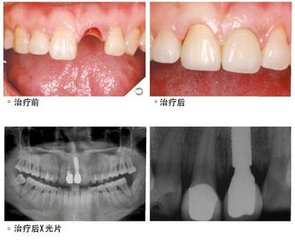

牙齿缺失不仅在老年人群中十分常见,而且一些青年人也往往因为口腔疾病、意外事故等原因导致牙齿缺失,给人们的生活带来极大不便。然而种植牙的出现,为广大缺牙患者带来了曙光,被誉为“人类的第三副牙齿”。那么,做种植牙要多少钱呢?

广州越秀圣贝口腔门诊部口腔介绍:目前种植牙的价格在几千以上,由于种植牙受患者病情、种植体材料等因素的影响,因此种植牙没有一个统一的价格。>>>了解更多收费详细?点击在线预约